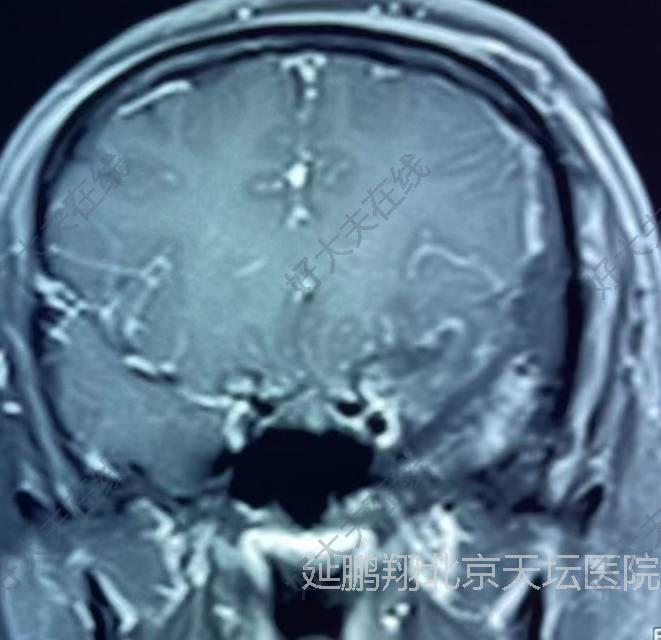

患者女性,38岁。间断性头痛3年左眼视力模糊1年。核磁显示左侧前床突脑膜瘤。

手术在全麻下进行,釆用左额颞入路,先切断肿瘤基底,阻断血供。肿瘤质地软,与脑组织粘连不紧,易分离,两者相隔有蛛网膜(图2),肿瘤切除后左侧嗅神经,视神经,颈内动脉,动眼神经均保护完好(图3)。

患者恢复顺利。复查核磁肿瘤消失。